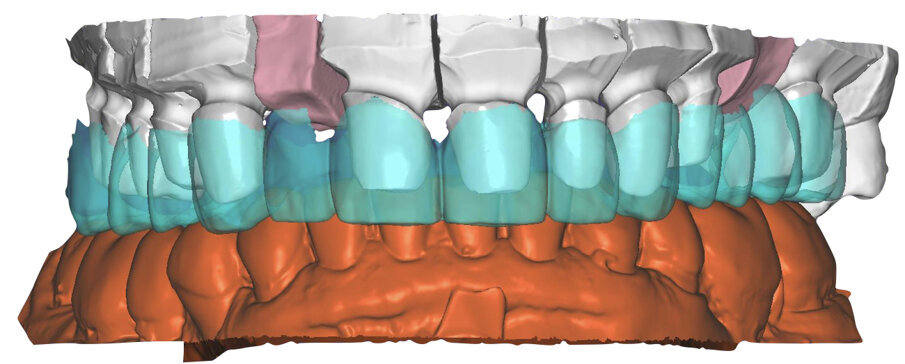

I modelli sono così importati in corretta posizione spaziale tramite il modulo exocad Virtual Articulator (Fig. 25). Non avendo a disposizione nel CAD l’analogo virtuale dell’articolatore Reference SL, viene impostato il sistema virtuale SAM, che usa lo stesso piano di riferimento axio-orbitale e geometria sovrapponibile al Reference SL. Per la programmazione virtuale dei parametri funzionali dell’articolatore si riesegue l’output dall’axiografia elettronica con Gamma Dental per SAM (Fig. 26). Si procede perciò ora con la modellazione CAD della ceratura mantenendo il riferimento dato dal piano occlusale individuato dai coni di centrica scansiti con l’articolatore (Fig. 27). L’articolatore virtuale consente una prima verifica dei rapporti occlusali tra gli elementi e un abbozzo di funzionalizzazione delle cuspidi con strumenti virtuali dinamici, che permette di arrivare ad un CAD design vicino alla morfologia ricercata (Figg. 28-33). Il modellato è ora fresato in cera Yeti Dental al CAM con fresatore VHF Cam5-S1 ed i denti in cera, tutti singolarmente sfilabili, sono posizionati sui modelli eseguiti con stampa 3D.

Il fresato ottenuto è poi riportato su articolatore Reference SL – già opportunamente programmato – e viene dall’Odontotecnico competente più precisamente funzionalizzato secondo i criteri della programmazione funzionale sequenziale, evidenziando con cere colorate i rapporti di centrica, le funzioni di mediotrusiva e protrusiva e le protezioni retrusive. I monconi sfilabili consentono la modellazione della sequenzialità mediotrusiva con la guida incisale indicata dalla registrazione axiografica (blu) (Figg. 34-37). La ceratura sequenziale è ora scansita con Sirona InEos X5 su Exocad, ed il modellato viene ricontrollato al CAD per spessori, connessioni e morfologia, e nella regolazione degli offsets per la ripreparazione dei monconi, ed è inviato al CAM per la fresatura dei II provvisori in Bredent breCAM.multicom, un PMMA con microriempitivo ceramico ad alta stabilità, su Dental Plus 5 Axis Milling Machine. La rifinitura dei monconi è seguita da ribasatura dei II provvisori in TRP - previo isolamento di tutte le superfici funzionali - e gli stessi sono poi rifiniti e lucidati. I soli elementi 3.3, 4.2 e 4.3 sono rimodellati in regione incisale con addictions in composito, secondo la morfologia studiata in ceratura. La consegna conferma la buona integrazione dei manufatti dal punto di vista estetico, occlusale, articolare e neuromuscolare, con controllo occlusale conforme al progetto (Figg. 38-42).

Il paziente utilizza questi secondi provvisori per otto settimane, durante le quali conferma la buona integrazione dei restauri e la soddisfacente funzione occlusale. Ciò è verificato con l’esecuzione di una nuova axiografia elettronica che già a due settimane dalla consegna evidenzia una buona risposta muscolare al nuovo design occlusale ed alla nuova postura mandibolare in TRP (Figg. 43-46). Provvediamo infine alle impronte per la costruzione dei manufatti definitivi in Zirconia-ceramica. I modelli sono scansiti in laboratorio con inEos X5 (Dentsply Sirona) su exocad (Figg. 47-49), ed una seconda scansione viene eseguita con i provvisori del Paziente posizionati sui modelli (Figg. 50-52). Il CAD consente di eseguire un matching fra le due scansioni, per cui i secondi provvisori utilizzati in TRP, con funzione occlusale sequenziale già completamente programmata, sono utilizzati per definire le morfologie dentali definitive di tutti gli elementi da restaurare (Figg. 53, 54) secondo il rapporto intermascellare definito (Figg. 55-58). Si esegue quindi fresatura al CAM della protesi definitiva in zirconia (Figg. 59, 60), la stratificazione e finitura ed infine la consegna al Paziente con cementazione in Panavia V5 (Figg. 61-65).